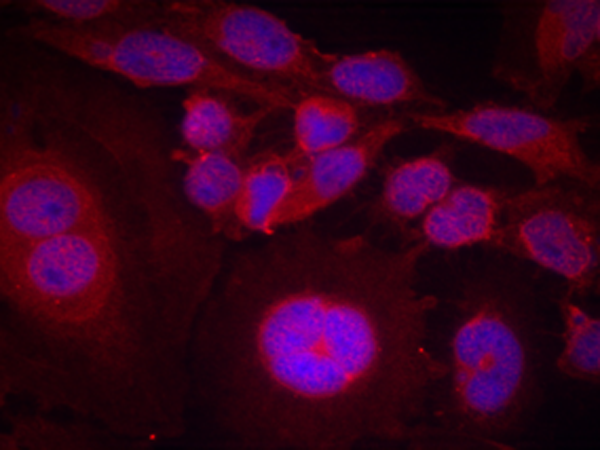

IF Positive control: |

Hela cells |

IF Recommended dilution |

100-200 |